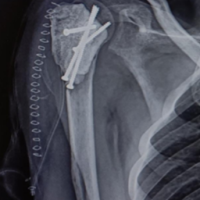

A C2–C5 double-door laminoplasty was performed. Post-operative computed tomography (CT) revealed a narrow lateral gutter at C3 and damage to the inner lamina, but adequate opening of the lamina was achieved, and the spacer was positioned appropriately (Fig. 1). In the current pre-operative plain radiographs, there was no deterioration in alignment, and no evidence of vertebral slippage or intervertebral instability (Fig. 2).

Figure 1: (a and b) Pre-operative images before the initial surgery. (a) Plain lateral radiographs Neutral position. No abnormal alignment or dynamic instability was observed. (b) Sagittal magnetic resonance imaging image. Spinal cord compression is evident at the C2/3, C4/5, and C5/6 levels. (c, d, e): Post-operative computed tomography after the initial surgery. (c) Sagittal view (d) Axial view at the C2 lamina level (e) Axial view at the C3 lamina level. Lamina inner plate damage at the lateral gutters is observed at both C2 and C3, but the spacers are well positioned, and sufficient laminar opening was achieved. At the C3 level, the lateral gutters were created medial to the medial pedicular line.